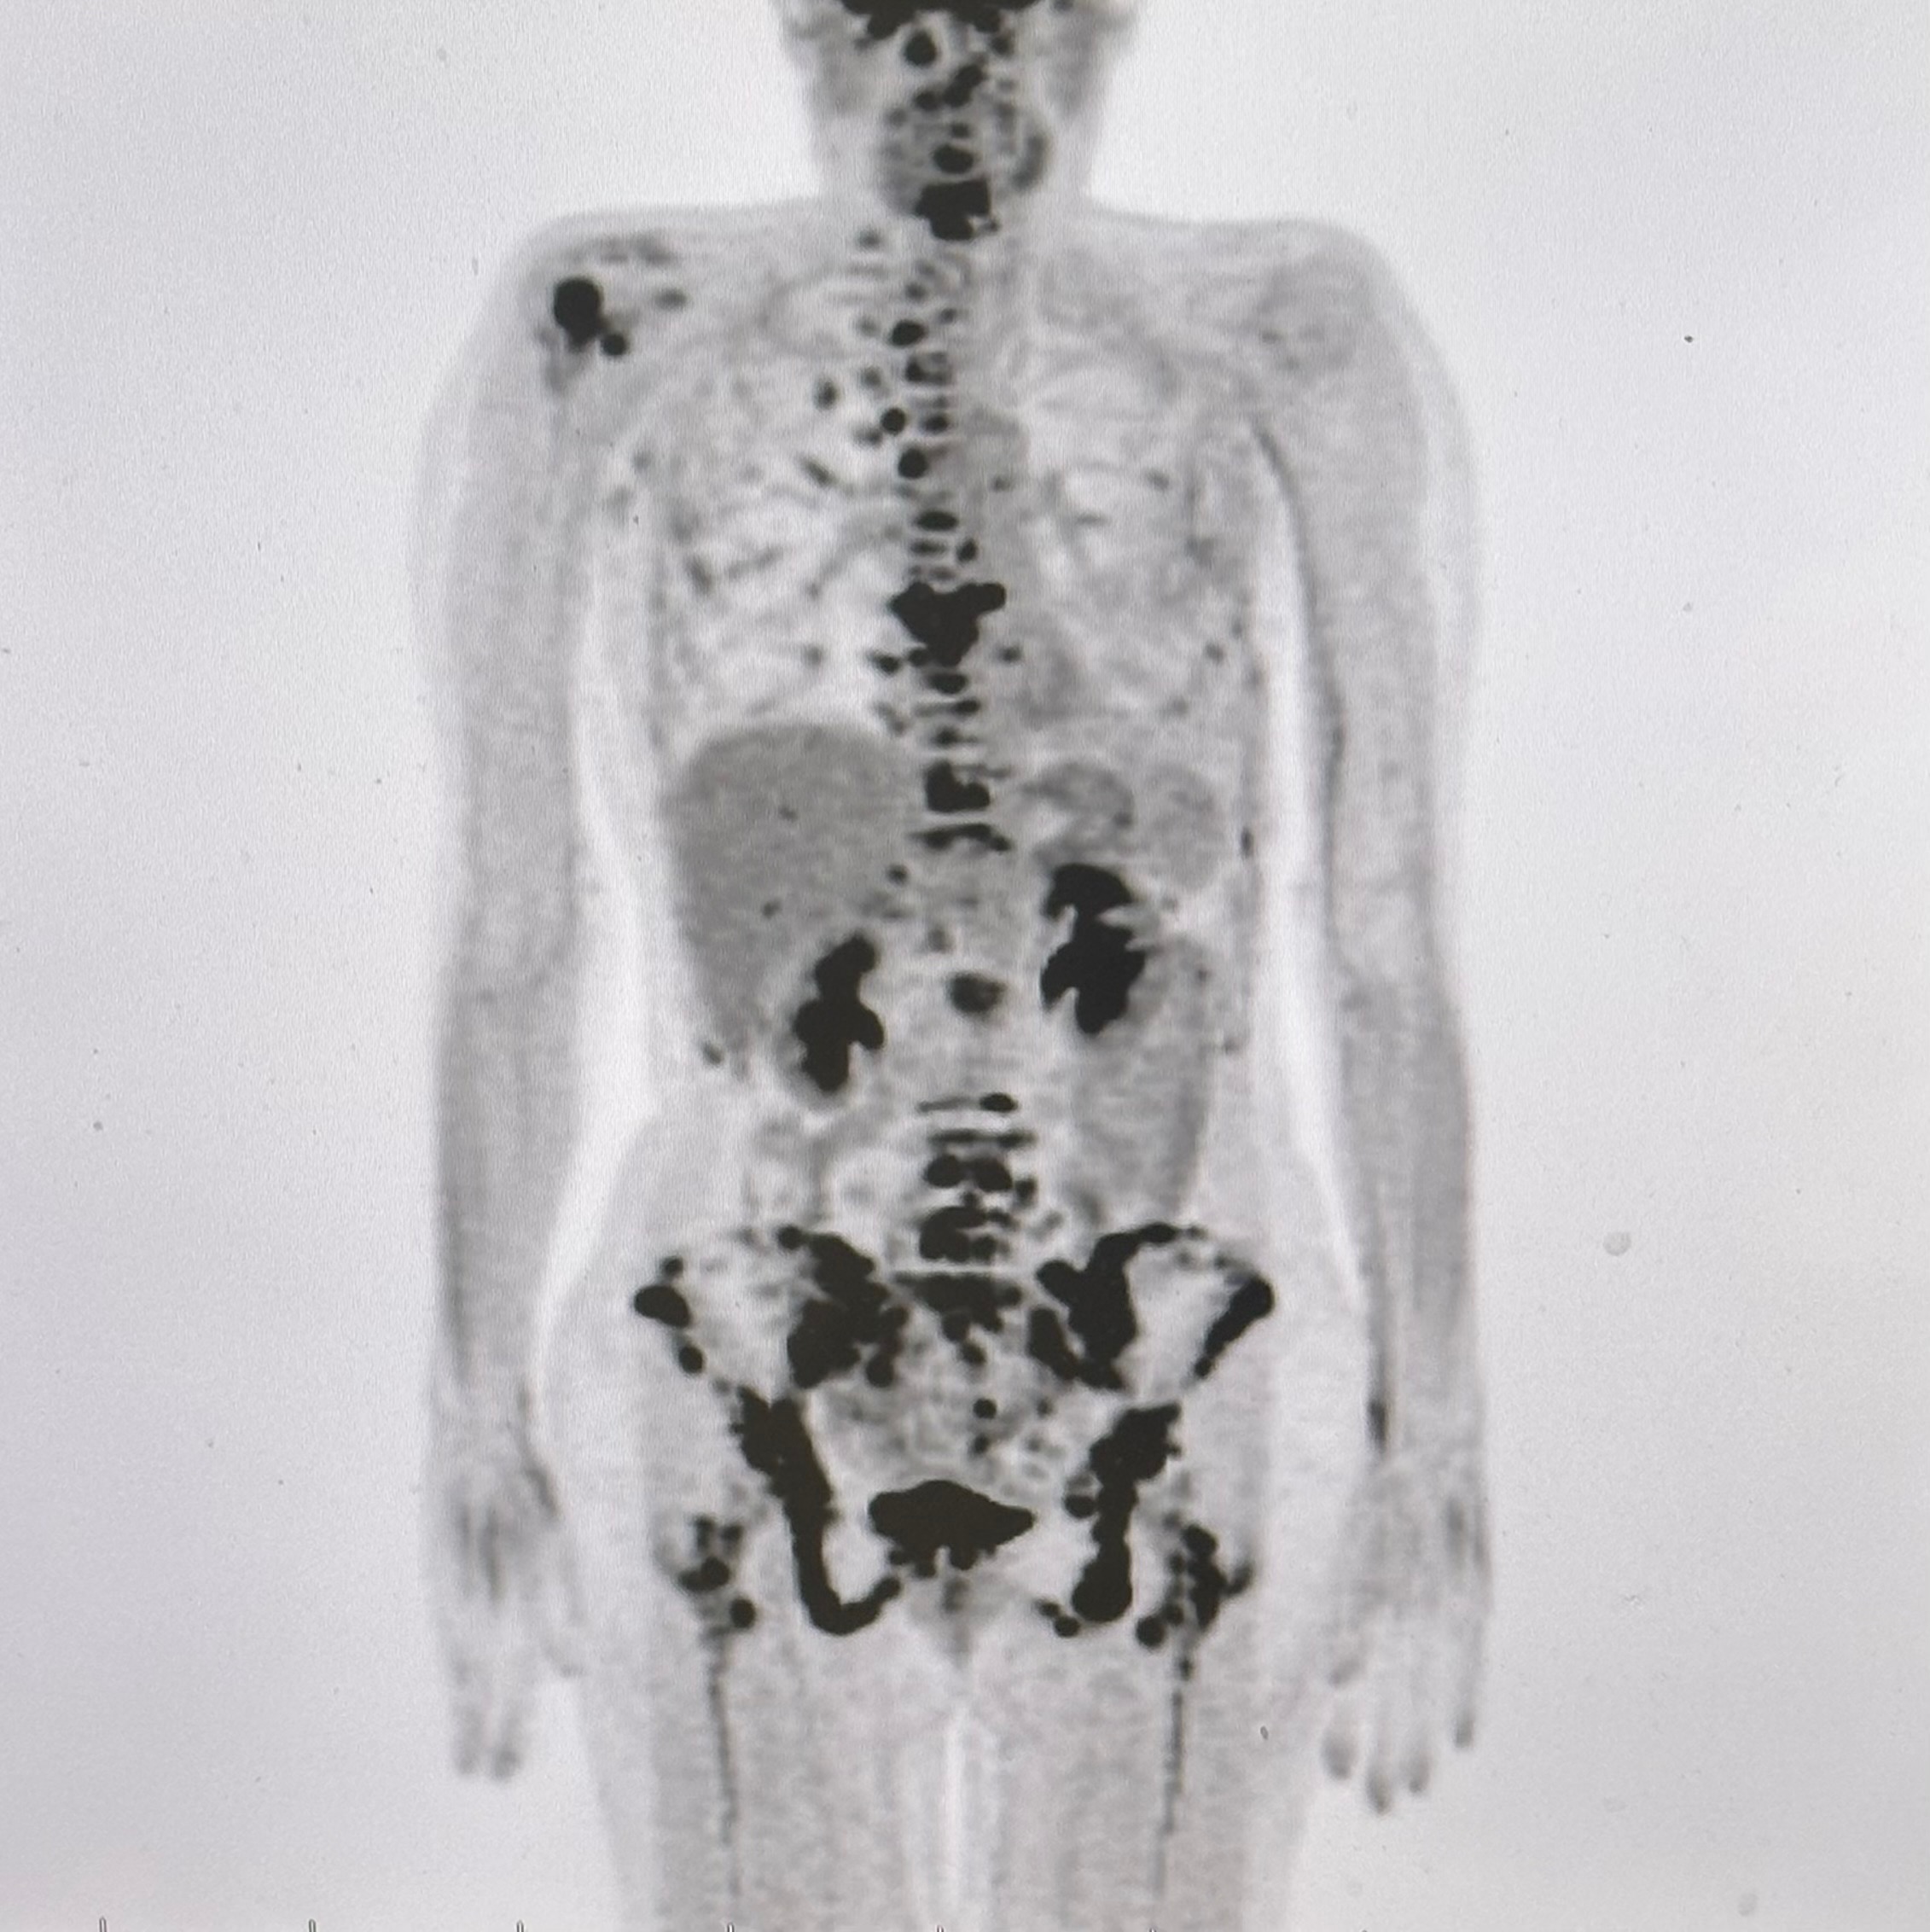

Recently her battle has become even more difficult. The cancer has metastasized to her bones.